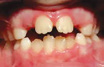

MORSO APERTO

Quando i molari chiudono tra loro, ma i denti anteriori non si toccano.